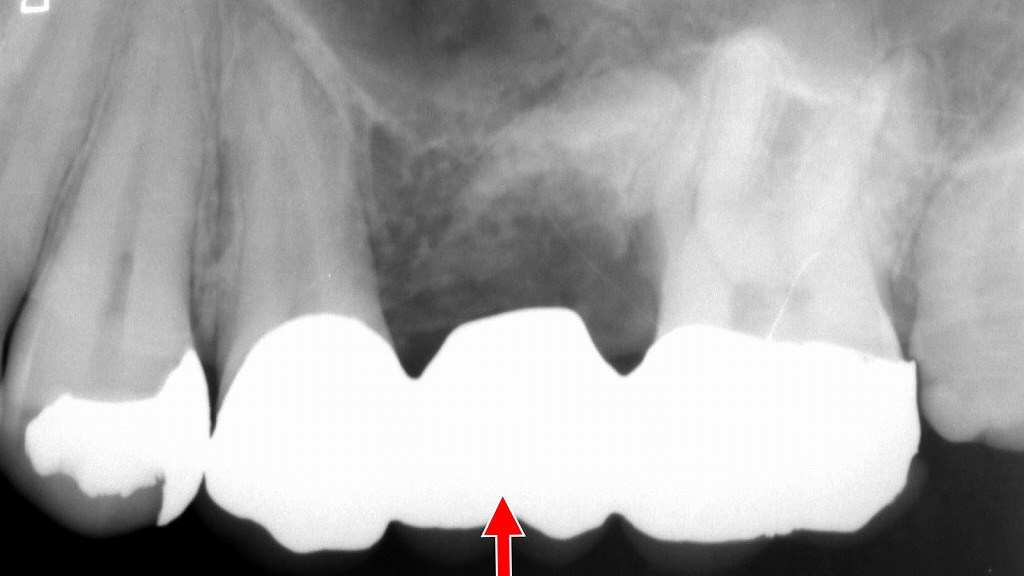

⚠️ 維持歯への負担と寿命への影響

部分入れ歯は、残っている歯(維持歯)にクラスプをかけて支える構造です。これにより、横揺れなどの負担が集中しやすく、歯槽骨が吸収されて歯がグラグラになる可能性も。維持歯の寿命が短くなるリスクがあるため、定期的なチェックが重要です。